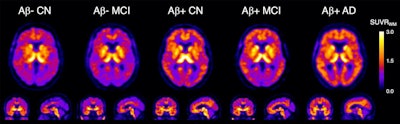

In this study, the group investigated the performance of F-18 SMBT-1 PET across the continuum of Alzheimer's disease, from groups of patients with beta-amyloid deposits who were cognitively normal to patients in later stages of the disease.

The researchers found no significant differences in F-18 SMBT-1 levels in beta amyloid-negative patients with mild cognitive impairment or who were cognitively normal. Conversely, F-18 SMBT-1 binding to MAO-B on reactive astrocytes was significantly higher in beta amyloid-positive Alzheimer's disease patients, according to the findings.

Most importantly, F-18 SMBT-1 binding was significantly higher in the same brain regions in beta amyloid-positive and cognitively normal patients compared to beta amyloid-negative and cognitively normal patients, the researchers stated. When all clinical groups were considered together, F-18 SMBT-1 was highly correlated with beta-amyloid burden, they concluded.